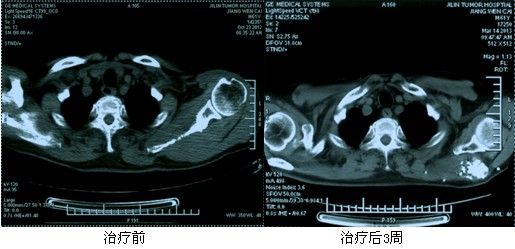

典型病例:姜XX,男,61岁,原发性肝右叶癌(BCLC C期)、多发性骨转移癌。左侧肩胛骨发生转移,左肩背部疼痛明显。给予125I放射性粒子植入后疼痛症状明显减轻,病灶明显萎缩。